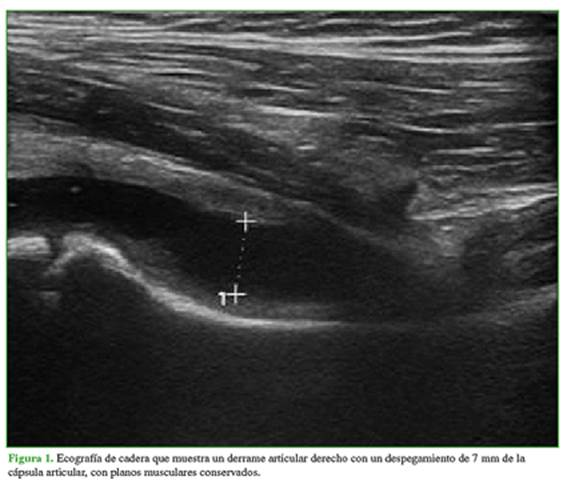

Se decidió internar al paciente para realizar una punción y drenaje del líquido articular y análisis bacteriológico. Por protocolo de internación de la institución, se realizó un estudio de reacción en cadena de la polimerasa para SARS-CoV-2, que fue positivo. Al indagar sobre un posible nexo epidemiológico, la madre refirió haber presentado síntomas compatibles con COVID-19 dos meses antes, por lo cual se le había indicado aislamiento domiciliario con su familia. Se efectuó una intervención quirúrgica y se tomaron muestras de líquido articular. En el momento de la punción, se obtuvo una muestra de líquido amarillento, claro, de consistencia viscosa. El paciente permaneció internado tres días, tuvo una buena evolución, y fue dado de alta, pero con indicación de aislamiento para él y los contactos estrechos que convivían en el domicilio. El análisis bacteriológico no informó desarrollo de gérmenes. El paciente evolucionó favorablemente una vez resuelto el cuadro viral. En el último seguimiento, el niño no tenía síntomas y el rango de movilidad de la cadera era completo. La radiografía no mostraba cambios en la articulación afectada (Figura 3).